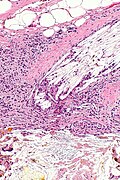

Xanthogranulomatous cholecystitis. H&E stain. | |

Features:[4]

- Granulomas.

- Lipid-laden macrophages.

- +/-Cholesterol clefts.

- Inflammatory cells.

- Fibrosis.

The sections show a thickened gallbladder wall with cholesterol clefts, multinucleated giant cells, fibrosis and lymphoid aggregates. No metaplasia, nuclear atypia or dysplasia is apparent.